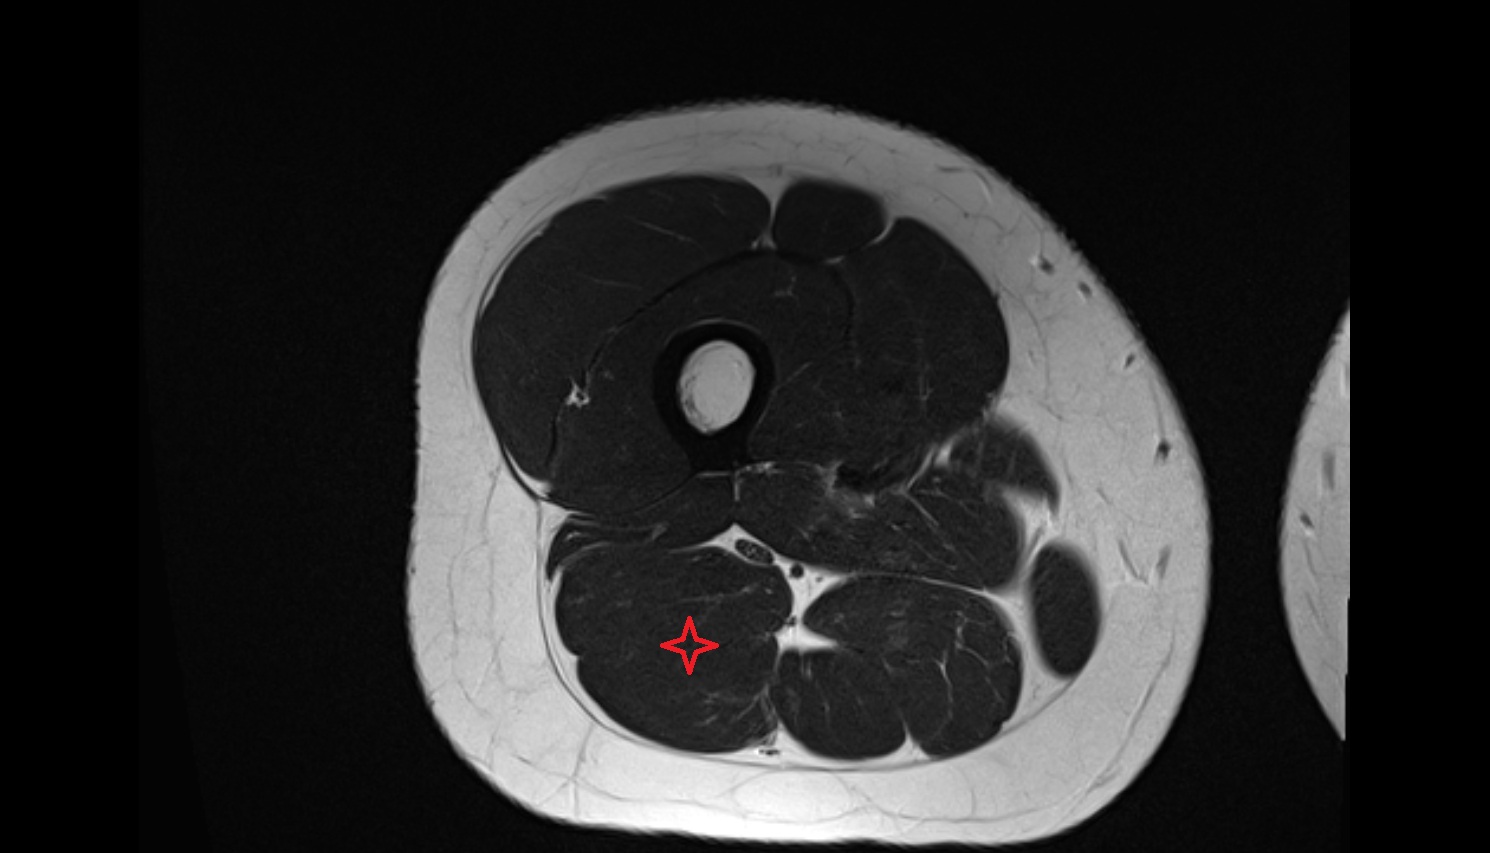

- Plantaris muscle

- Lateral head of gastrocnemius muscle

- Medial head of gastrocnemius muscle

- Gastrocnemius muscle

- Popliteus muscle

- Soleus muscle

- Biceps femoris muscle (Short head)

- Biceps femoris muscle (Long head)

- Semitendinosus muscle

- Semimembranosus muscle

- Body of tibia

- Tibia

- Fibula